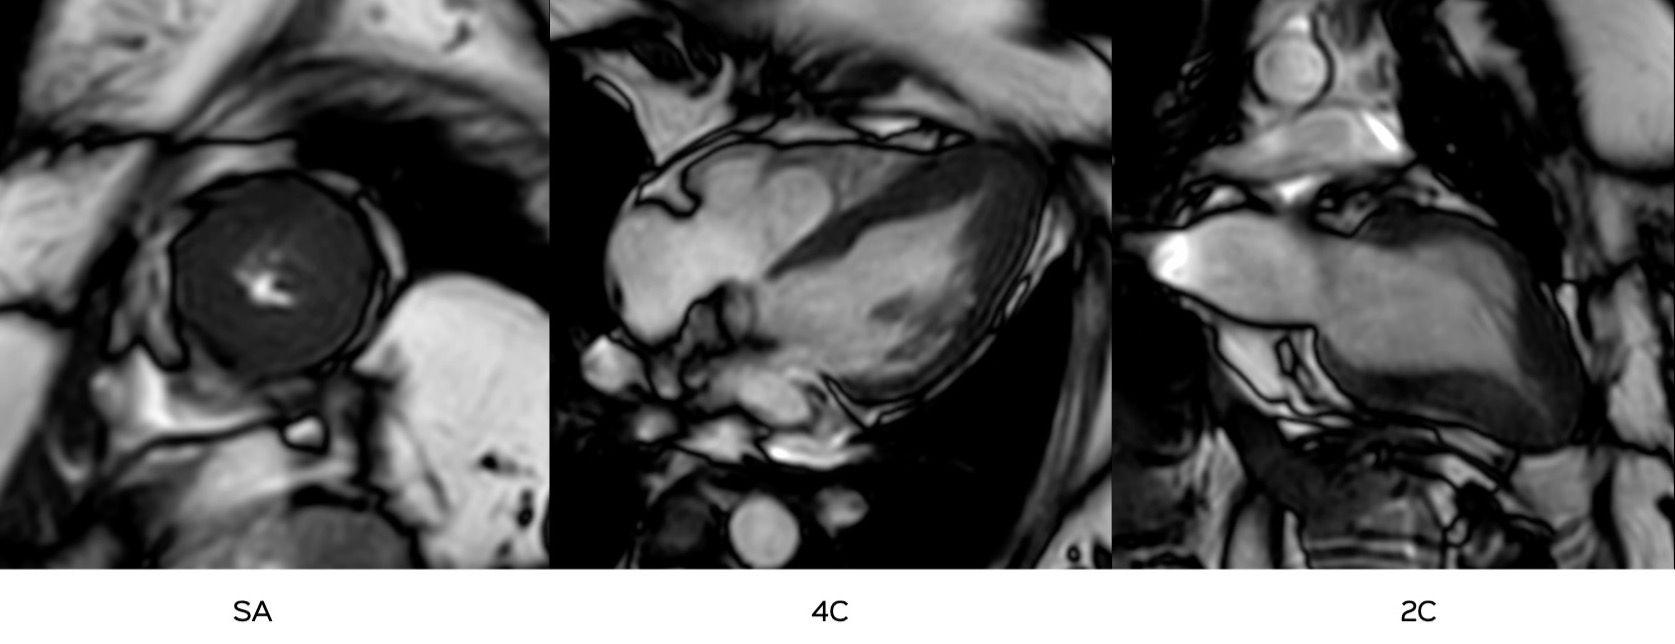

This is a 56-years old who presented with chest discomfort and echo showed apical thickening.

What do you think is the diagnosis?

- Fabry's

- Amyloidosis

- EMF

- Apical hypertrophic cardiomyopathy